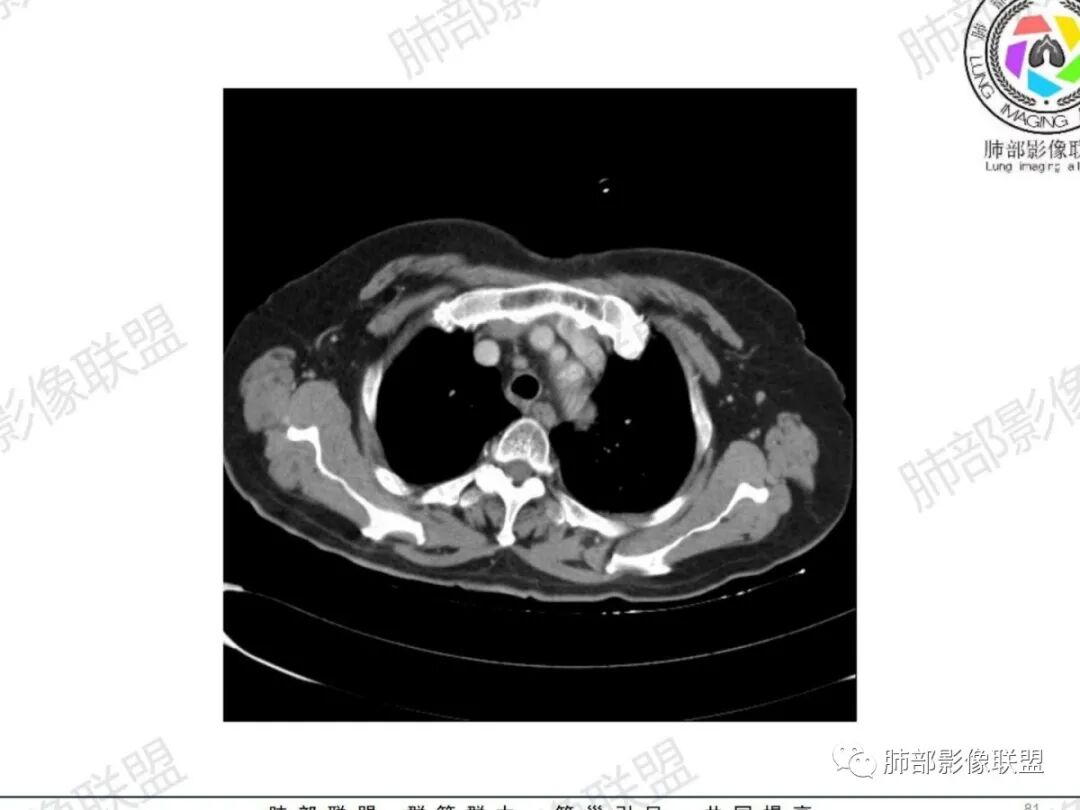

气管右后侧壁结节,结节向气管腔内突出,气管壁增厚,轻度强化,左侧甲状腺占位,考虑气管原发肿瘤,腺样囊性癌?类癌?

老年人,气管后壁结节,部分突腔外,考虑恶性,腺样囊性癌可能大,鉴别炎性肌纤维母细胞瘤

无蒂,无颈,气管侧后壁(特殊部位),虽然是老年女性年龄不符合,但是腺样囊性癌仍做首要考虑,还要考虑鳞癌。

1.定位:软骨中断,非外压,而是气管本身起源,考虑恶性。与之鉴别是周围间叶起源的神经源性或平滑肌起源良性肿瘤

气管右后壁占位,平扫密度稍低于肌肉

内外边缘光滑

宽基底与气管相连

附近壁增厚

宽基底,腔内外,看似边界清楚、光滑, 但是附近气管壁增厚,还是首先要考虑恶性,附近淋巴结也不太放心,因为强化明显